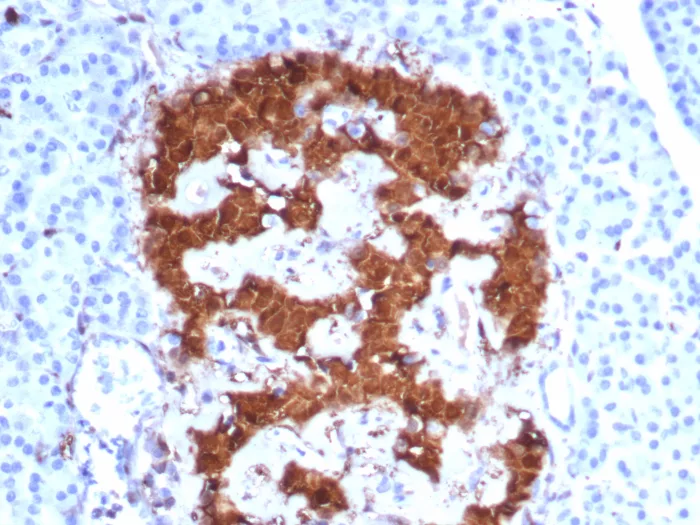

Formalin-fixed, paraffin-embedded human pancreas stained with Pgp9.5 Mouse Monoclonal Antibody (UCHL1/8152). HIER: Tris/EDTA, pH9.0, 45min. 2°C: HRP-polymer, 30min. DAB, 5min.